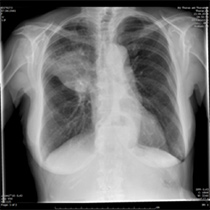

Lungenkrebs Behandlung

Lungenkrebs Lungenkazinom